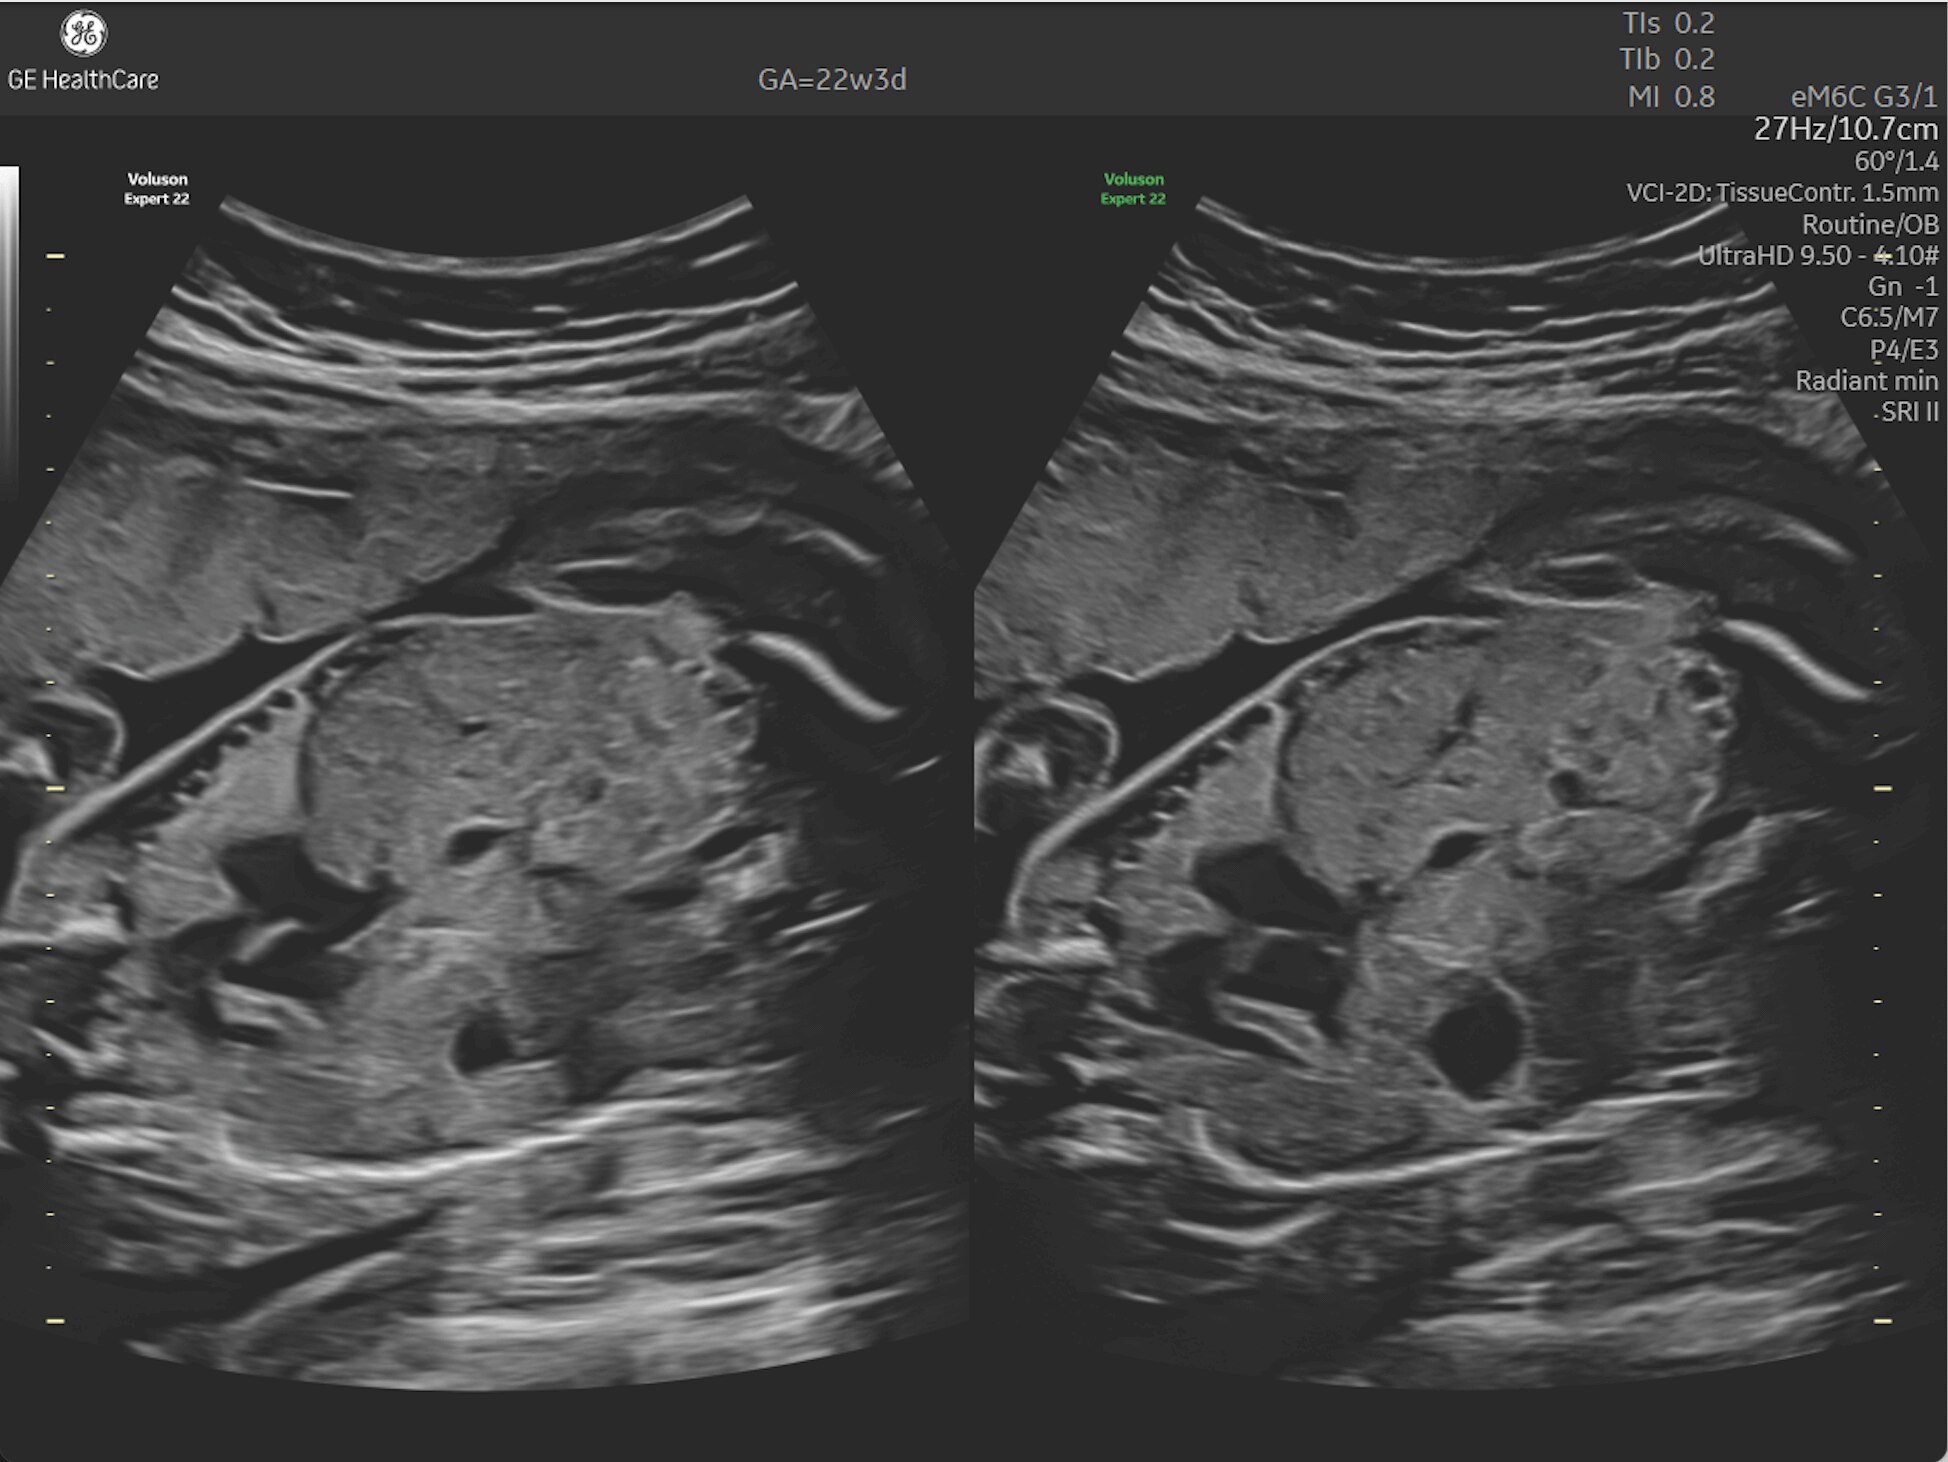

First Trimester Exams

Perform detailed exams with high-resolution for early insights to fetal health

Fetal Heart Assessment

Detect, diagnose, and monitor with confidence using Radiant and fetal HQ